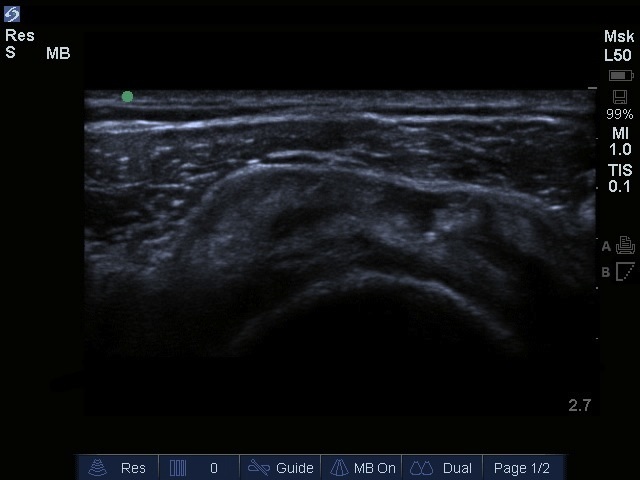

肩袖撕裂横断面图像